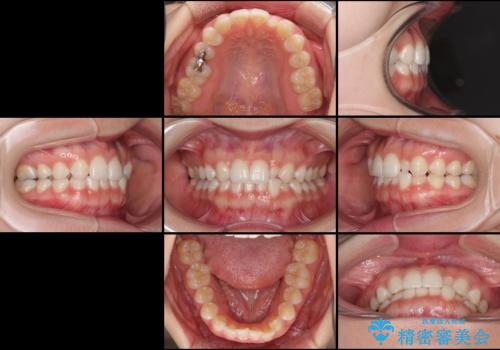

- 1年後に海外に転居するため、気になる前歯を矯正治療で整えたいとのことで来院された患者様です。

下顎は叢生が強かったため、奥歯までワイヤーを装着し、上顎は前歯の一部のみ気になっていたので、その部分にだけワイヤー装置を装着することとしました。

部分矯正は、適応となる症例が限定されます。

こちらの患者様は部分矯正が可能な、非常に珍しい方でしたが、部分矯正を希望される患者様の大半は、全顎矯正が必要となります。

安易に部分矯正を受けると、予想もしていなかった仕上がりとなることがあるので注意が必要です。